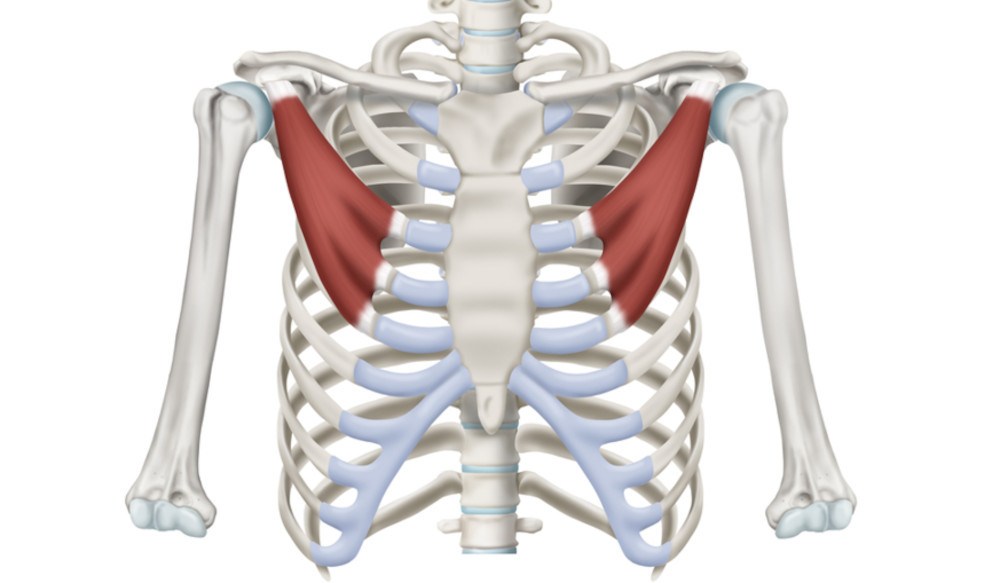

Quando portiamo il braccio e la mano il più possibile verso il gomito e il braccio opposti, la spalla si sposta leggermente in avanti e, soprattutto, verso la linea di mezzo del nostro corpo. Quando si trova in questa situazione, la spalla si dice addotta. Un ruolo determinante in questo movimento lo ha il muscolo pettorale. Se quest’ultimo è in stato di spasticità, la spalla rimane addotta.

L’adduzione della spalla causata dalla spasticità del muscolo pettorale forza l’articolazione producendo dolore, a volte intenso e persistente. Questa condizione non è rara dopo un ictus, ma può presentarsi anche nei bimbi, in esito di paralisi cerebrale.

Nei bambini c’è un problema aggiuntivo: la spalla ha un ruolo determinante nel controllo della postura, e tende inoltre a chiudere il torace, con possibili problemi respiratori negli anni a seguire.

Ottenere il rilasciamento di questo muscolo è particolarmente difficile, e la persistenza della spasticità tiene vivo il dolore, aprendo la strada a problematiche posturali importanti nei bambini, ostacolandone fortemente la riabilitazione.